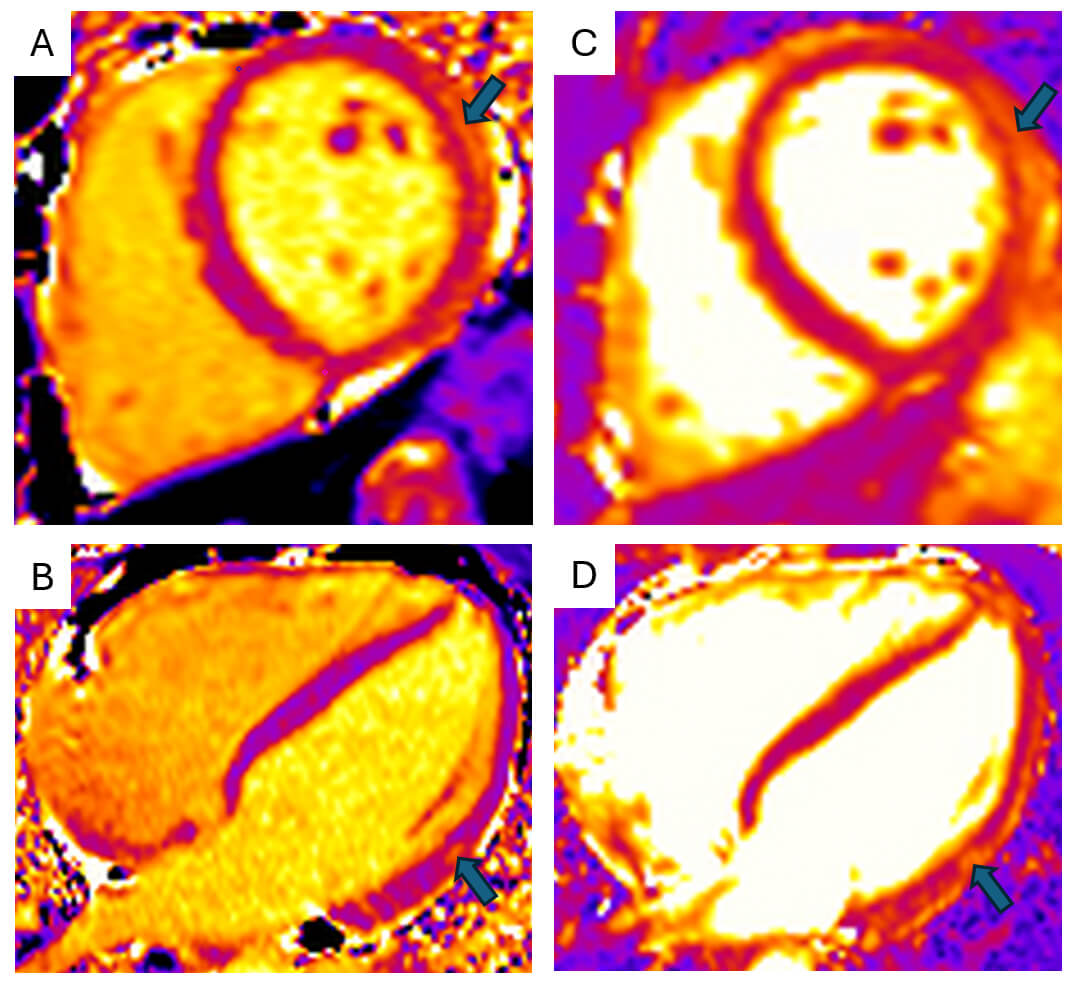

The advantages of parametric mapping lie in the ability to provide spatial visualisation and quantification of myocardial tissue changes seen in myocarditis. This allows for better assessment of diffuse disease processes and the study of the evolution of the disease process. T1 mapping measures the longitudinal relaxation time (T1), which is frequently elevated in myocarditis due to oedema, necrosis, or interstitial expansion associated with inflammation (Fig. 2A,B). Native, pre-contrast, T1 mapping is particularly useful for detecting diffuse myocardial oedema or fibrosis that may not be apparent with conventional imaging. It is therefore sensitive, but lacks specificity for the assessment of oedema. T2 mapping quantifies transverse relaxation time (T2), and elevated values serve as a more specific marker for myocardial oedema (Fig. 2C,D). Extracellular volume (ECV) is derived from pre- and post-contrast T1 mapping values and reflects extracellular matrix expansion and is elevated in areas of oedema or scar [30]. Utilising the combination of these three values allows for a comprehensive assessment of areas of myocardial scar and oedema, with the presence of elevated ECV, T1 and T2 being associated with adverse events in myocarditis, including arrhythmia and cardiac mortality [31].

Fig. 2.

Cardiac magnetic resonance parametric mapping. Cardiac magnetic

resonance imaging (MRI) T1 (A,B) and T2 (C,D) mapping of the myocardium in mid

short-axis (A,C) and four-chamber (B,D) views demonstrates focal increases in

relaxation times (T1 = 1281 ms; T2 = 63 ms) within the mid-lateral and

infero-lateral walls (arrows). Images acquired on Siemens Aera 1.5T scanner

(Siemens, London, England) (normal ref range T1